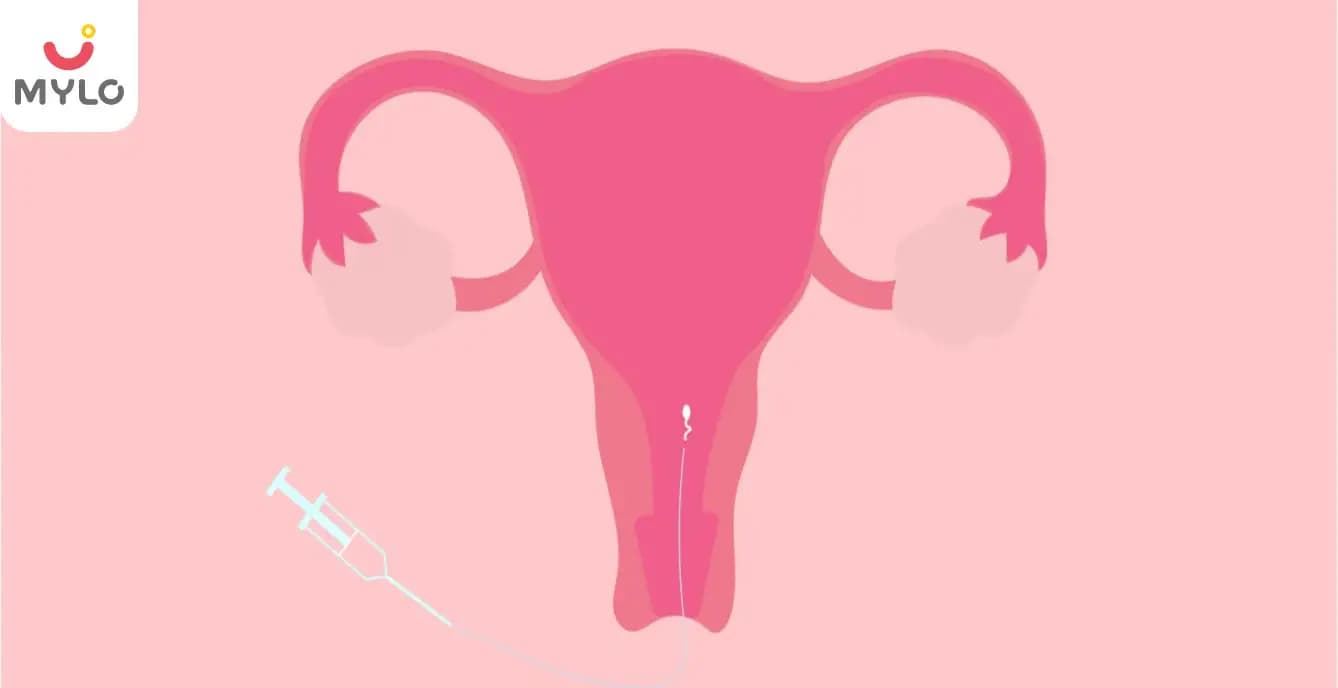

Is IUI (Intra Uterine Insemination) Painful?